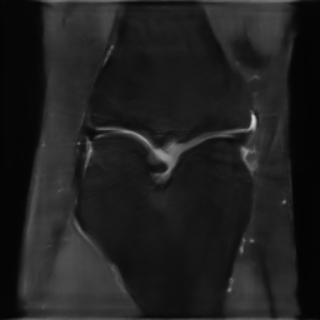

This article presents a novel undersampled magnetic resonance imaging (MRI) technique that leverages the concept of Neural Radiance Field (NeRF). With radial undersampling, the corresponding imaging problem can be reformulated into an image modeling task from sparse-view rendered data; therefore, a high dimensional MR image is obtainable from undersampled $k$-space data by taking advantage of implicit neural representation. A multi-layer perceptron, which is designed to output an image intensity from a spatial coordinate, learns the MR physics-driven rendering relation between given measurement data and desired image. Effective undersampling strategies for high-quality neural representation are investigated. The proposed method serves two benefits: (i) The learning is based fully on single undersampled $k$-space data, not a bunch of measured data and target image sets. It can be used potentially for diagnostic MR imaging, such as fetal MRI, where data acquisition is relatively rare or limited against diversity of clinical images while undersampled reconstruction is highly demanded. (ii) A reconstructed MR image is a scan-specific representation highly adaptive to the given $k$-space measurement. Numerous experiments validate the feasibility and capability of the proposed approach.